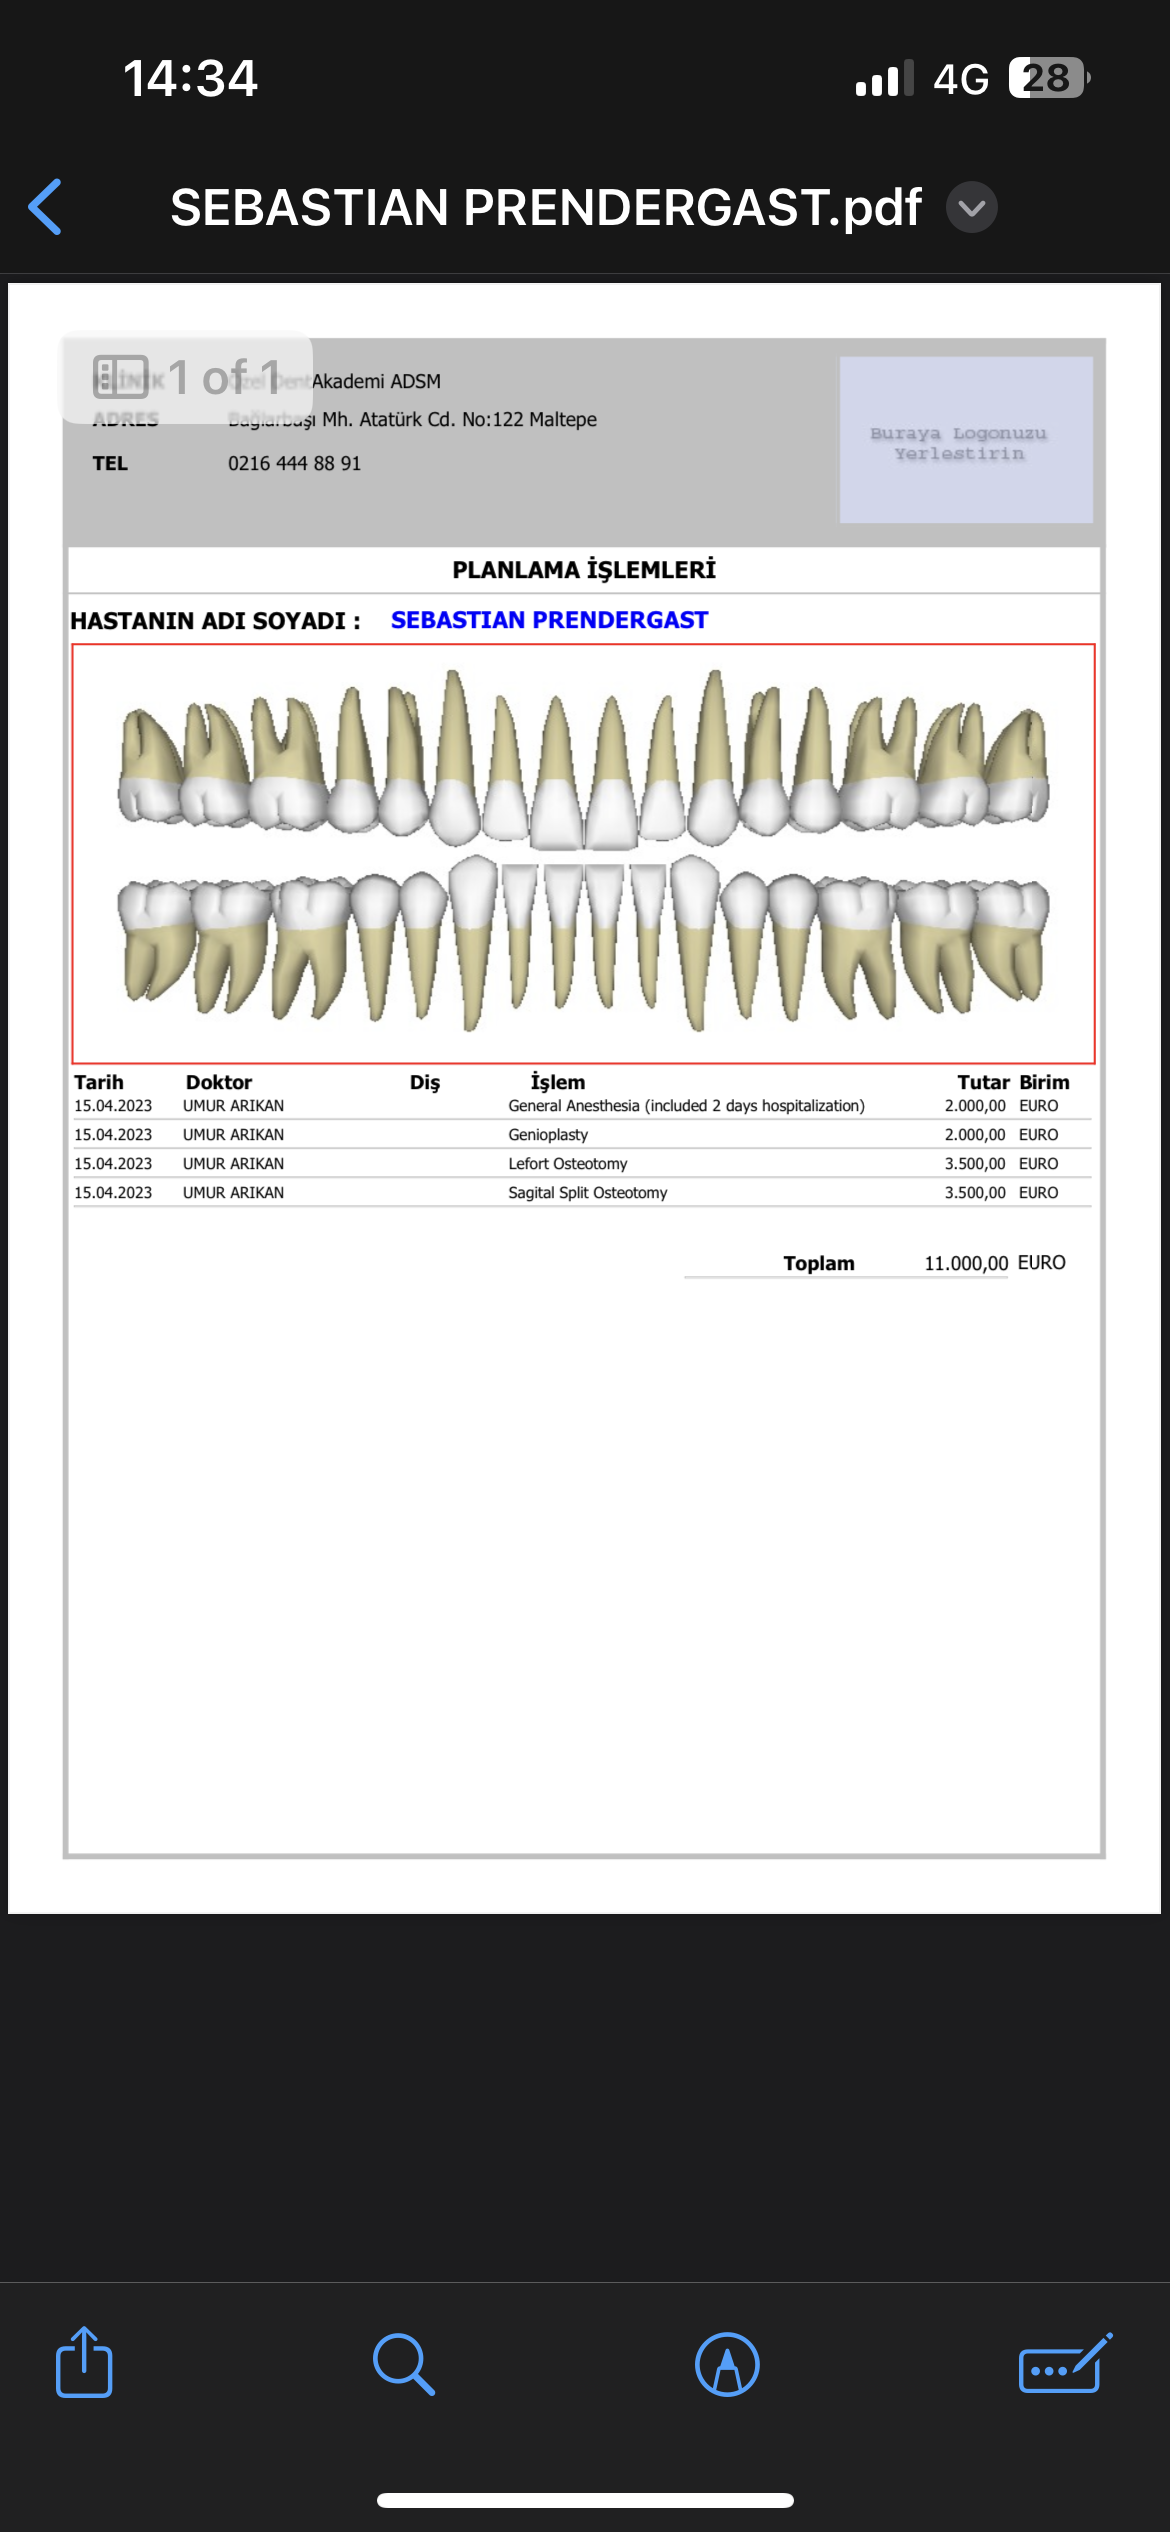

Who knows of good surgeons in either Turkey or maybe Poland who could realise such results? (Not touching eyes, just nose + chin)

I have money to book but want a good price. No botch jobs